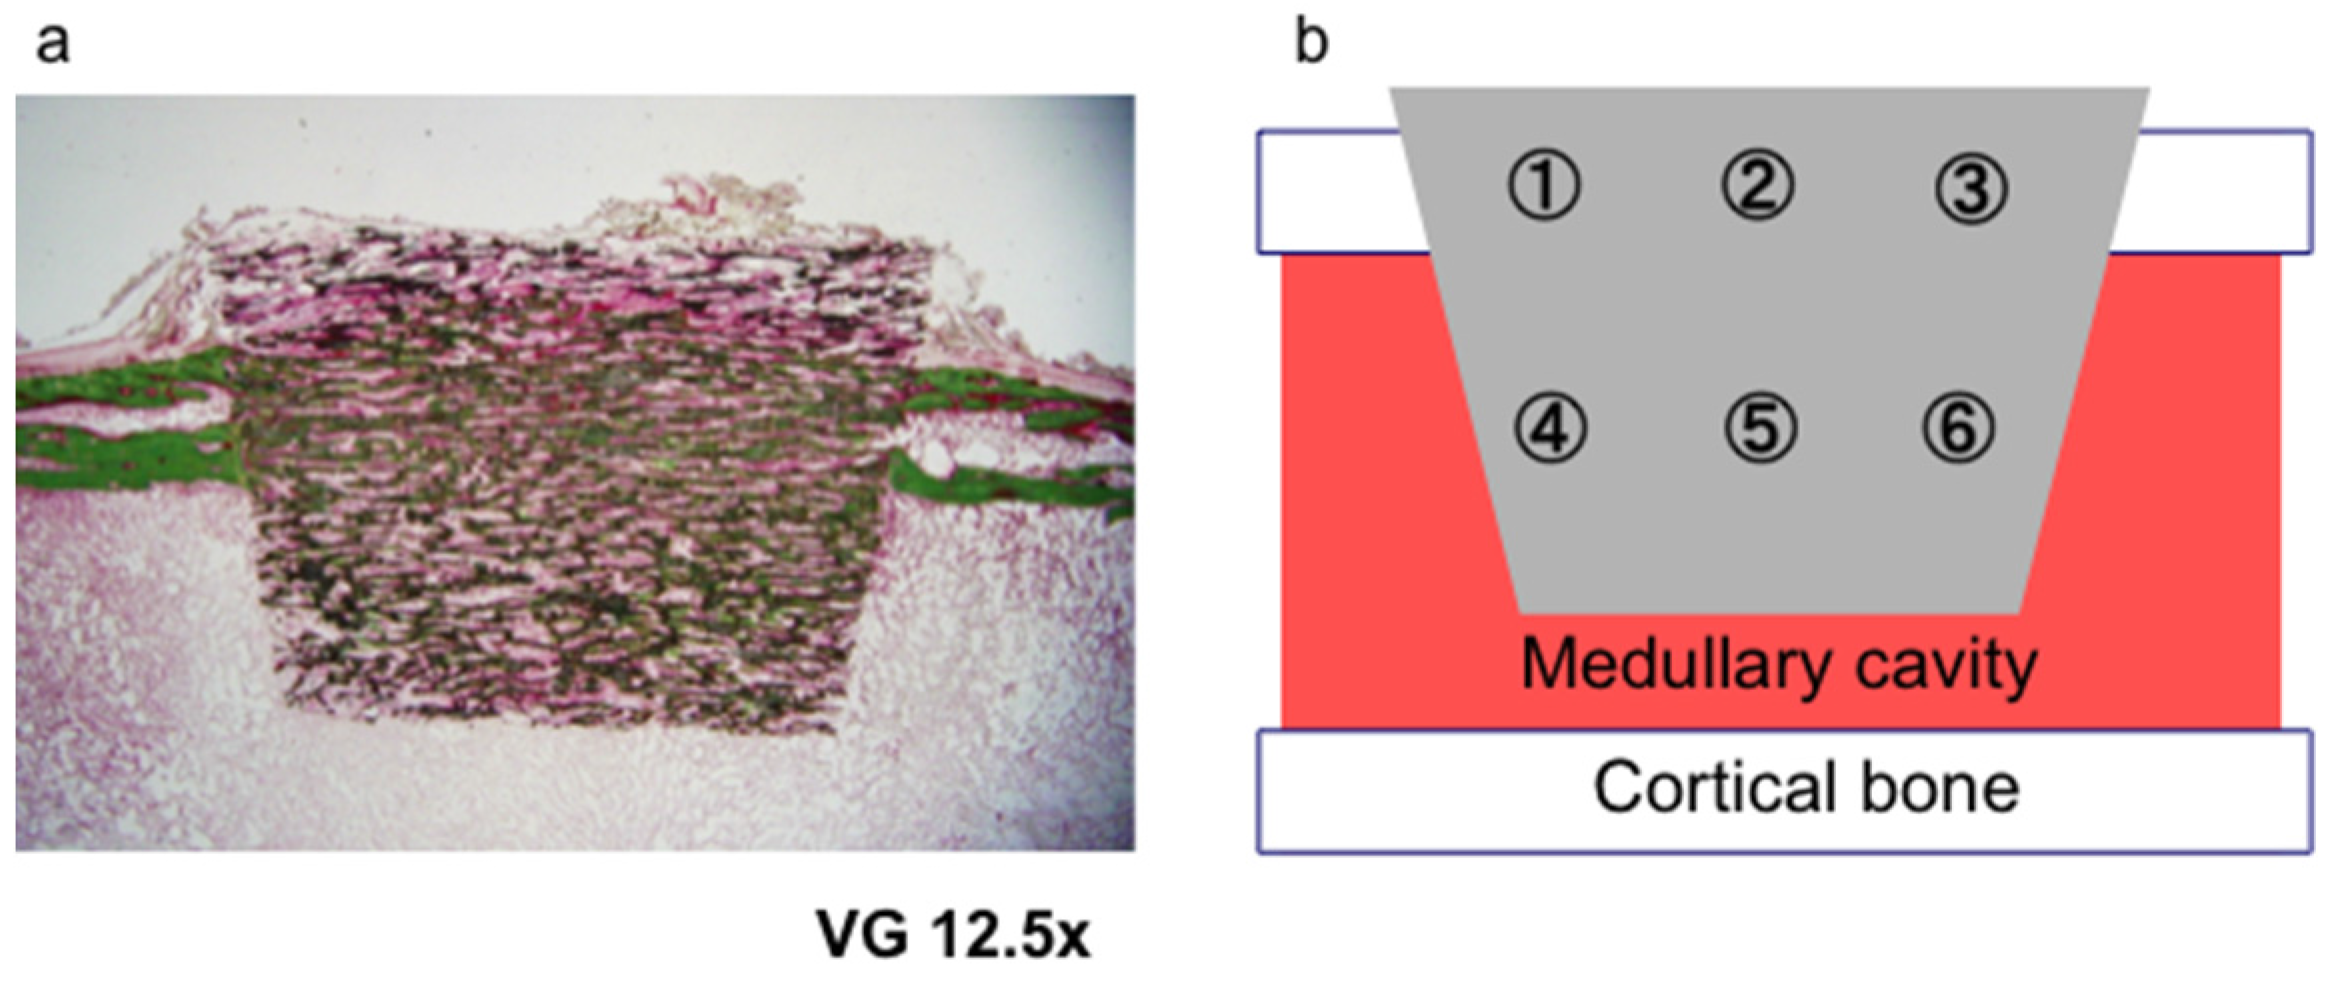

2. Results and Discussion

3.2. Histological Analysis

3.3. Bone Formation in Cortical and Medullary Bone Regions